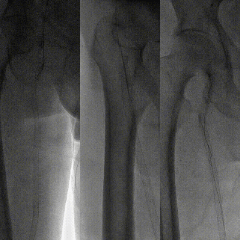

右股总-髂外闭塞,左股-腘动脉全程闭塞,膝下流出道显示不清,重度钙化

图:术前CT

图:造影显示,股腘动脉全程闭塞,膝下流出道差